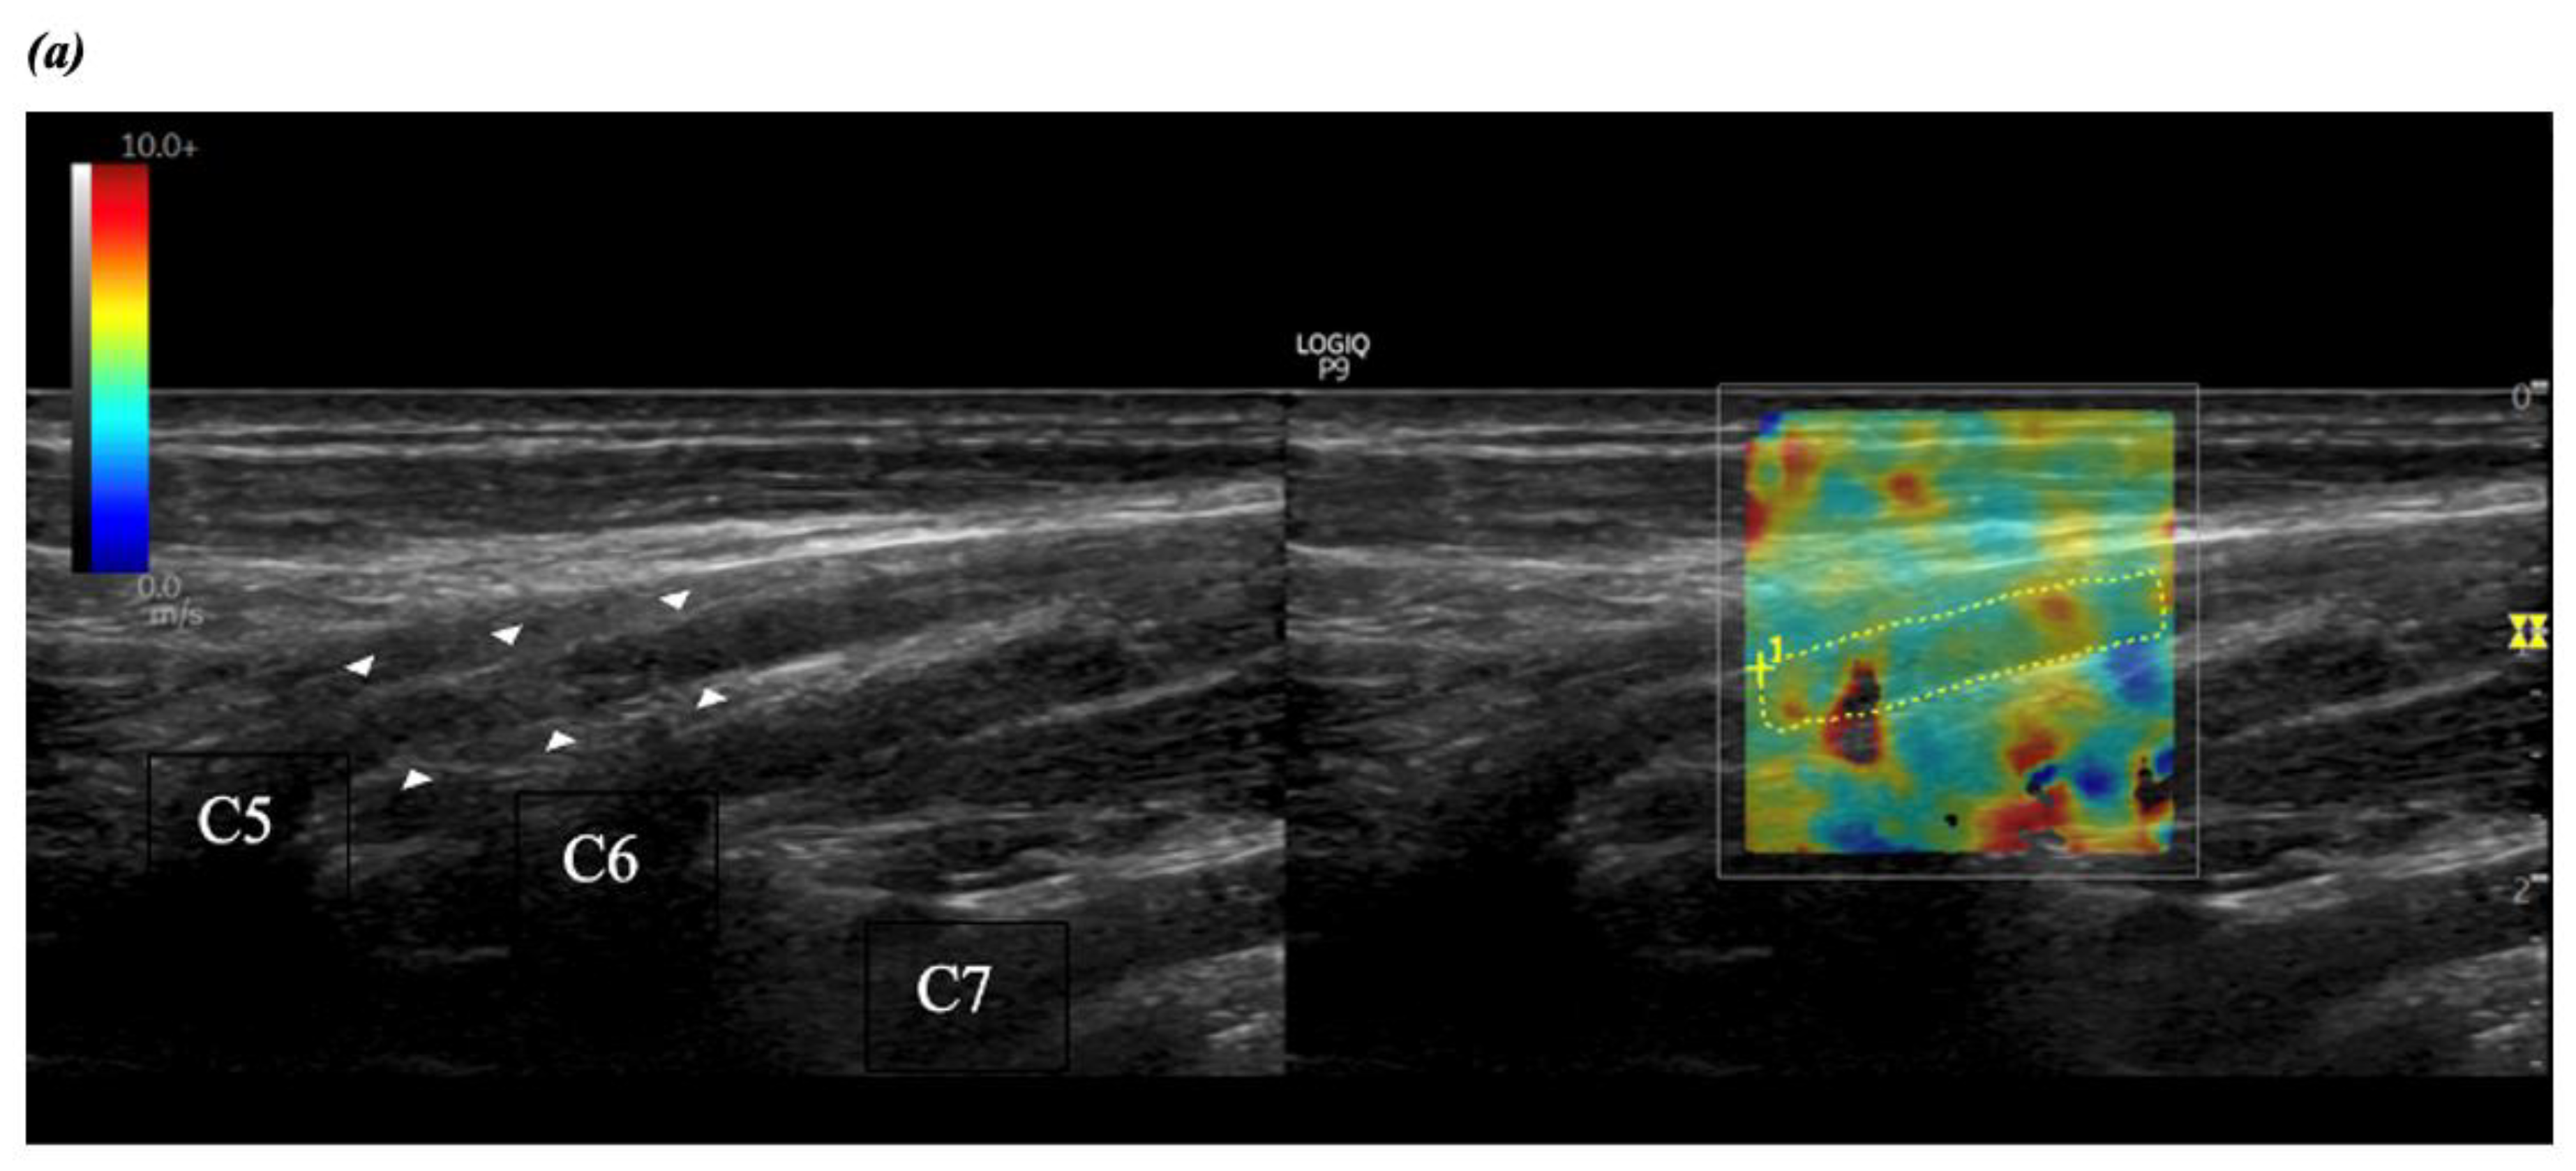

2.2.2. Brachial Plexus Imaging

2.2.3. Shear Wave Elastography and Ultrasound Measurements